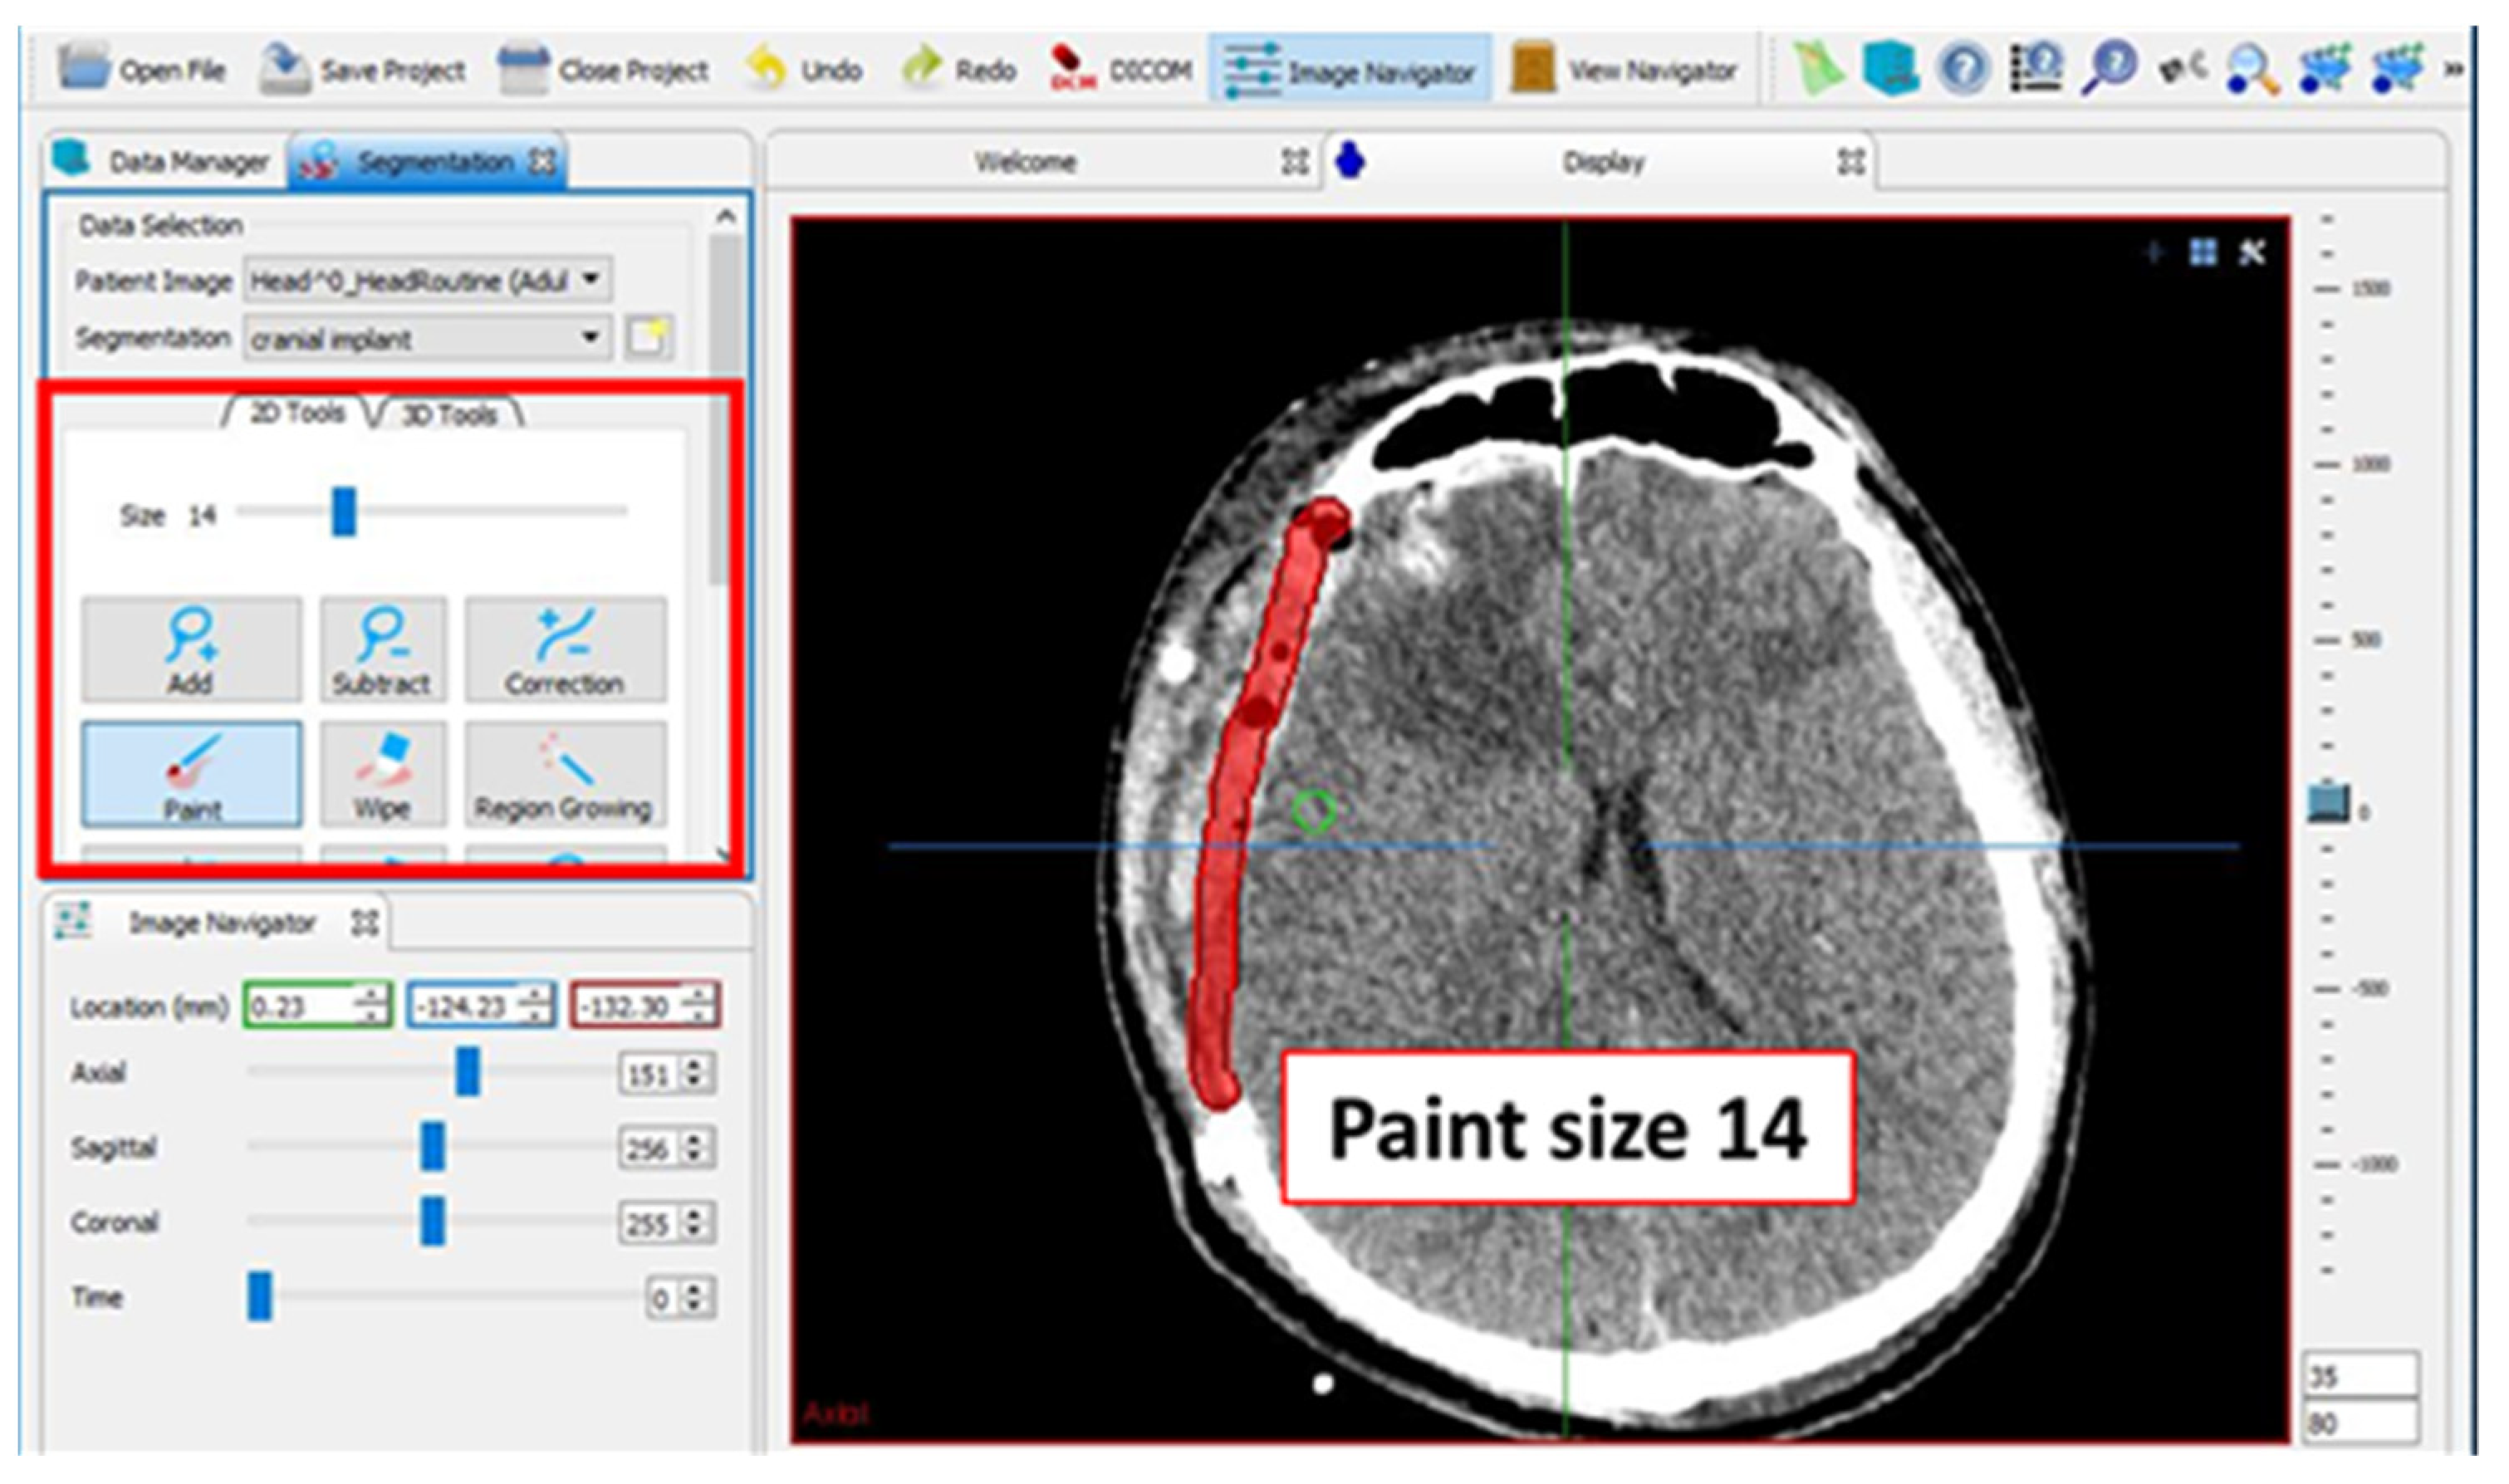

2.2. Design of Cranial Implants Using MITK Software